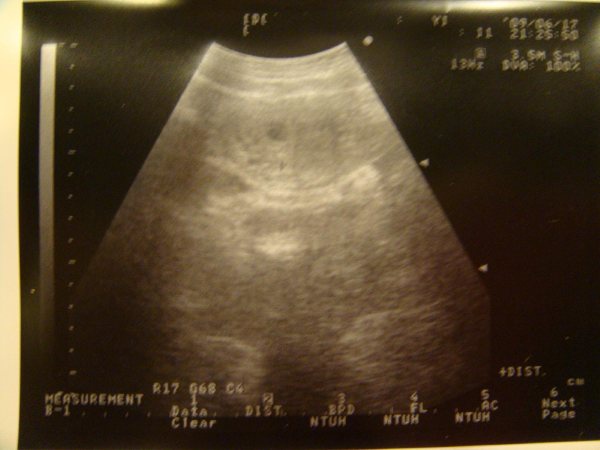

[註1]6W時於國泰醫院第一次照超音波,至今依然記得當時看到胚胎著床影像時的悸動與欣喜...

7W時於馬偕醫院照了第二次超音波,第一次看到baby跳動的小心臟,也是從那天起我們

更真實地感受到一個小小的生命逐漸地在我的肚子裡醞釀著、成長著....